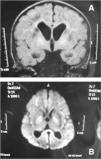

Se realizó estudio microbiológico para virus y bacterias con resultado negativo. El estudio metabólico fue normal. En la ecografía cerebral, se detectaron lesiones en la región talámica que indicaban un proceso de desmielinización y que se acompañaban de un edema cerebral. En la resonancia magnética (RM) cerebral se observaron cambios de necrosis hemorrágica subaguda yuxtacortical (fig. 1A). El estudio de difusión indicó edema citotóxico (fig. 1B). En el momento del ingreso, el paciente requirió estabilización con fármacos vasoactivos e inotrópicos y por fallo ventilatorio agudo, conexión a ventilación mecánica, mantenidos 4 días. Precisó infusión de bicarbonato y tratamiento con hemoderivados por CID. Recibió antibioterapia de amplio espectro y tratamiento con cofactores. Presentó un fallo renal agudo con anuria e hipercalcemia, por lo que se inició terapia con depuración extrarrenal con hemodiafiltración venovenosa continua durante 4 días. A las 24 h, inició un fallo hepático agudo con incremento moderado de transaminasas y coagulopatía grave, que remitió iniciando mejoría analítica a los 3 días y normalización a los 10 días. La evolución fue favorable; fue dado de alta a los 20 días, aunque persistieron importante irritabilidad, desconexión del medio, hipertonía de las cuatro extremidades e inclusión de pulgares. A los 4 meses, continúa presentando tetraparesia espástica y retraso psicomotor.

Durante su ingreso, se realizaron varias pruebas de imagen. En la ecografía cerebral inicial se observaba un importante edema, tratado con medidas antiedema. Las imágenes de la RM en estadio subagudo con afectación de la sustancia blanca y de la sustancia gris subyacente eran similares a la descritas recientemente por Toyoshima et al8 y a las encontradas en la encefalopatía por virus del herpes 69 y en el síndrome hemiconvulsión-hemiplejia10.

En conclusión, todavía se desconocen muchos aspectos de este síndrome. La principal herramienta para su diagnóstico es la sospecha clínica. La difusión en RM demuestra una afectación temprana de la sustancia blanca y podría ser clave para un diagnóstico de certeza precoz.